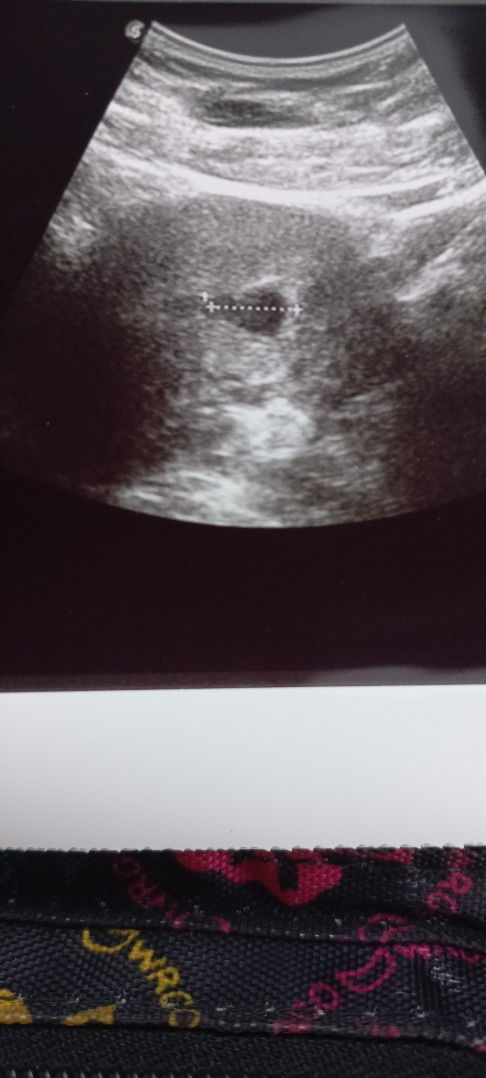

Mama keliru

Hai mommies..ikutkan tarikh period saya dah 8w5d...tp scan kat klinik baru 5w2d.kenape berbeza ya..tu pun nampak kantung sahaja..doktor pun belum comfirm yg kandungan saya menjadi..rasa down sangat..harap sgt yg saya ade rezeki..sbb dah lama tunggu..anak sekarang pun dh umur 8 tahun